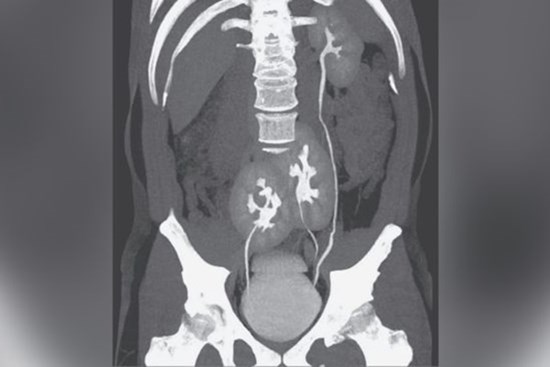

Bị đau lưng, người đàn ông đi khám mới biết mình có tới 3 quả thận

Một người mà có tới 3 quả thận là trường hợp rất hiếm gặp, trong tài liệu y khoa, số ca bệnh này còn chưa đến 100.